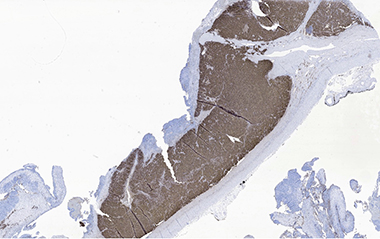

Synaptophysin and chromogranin were positive in pheochromocytoma areas. S100 and neurofilament were focally positive in spindle cell areas and sustentacular cells. Vimentin was positive in spindle cell areas. H3K27me3 showed focal areas with loss of expression. Inhibin was positive in focal areas, consistent with entrapped cortical cells.

F. Pheochromocytoma with positive chromogranin stain